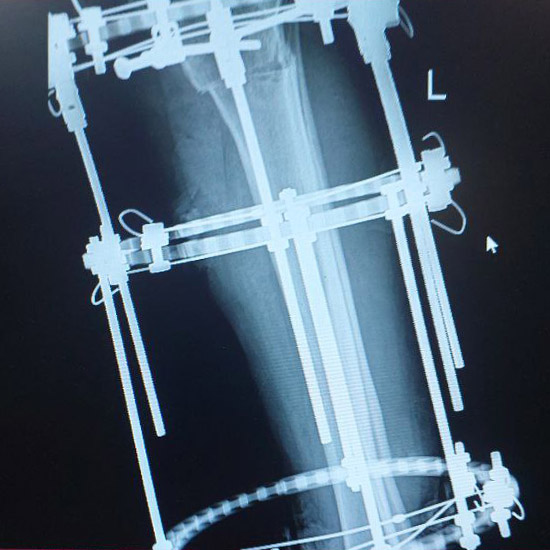

بخشی از نمونه کارها

نمونه کارهای قبل و بعد